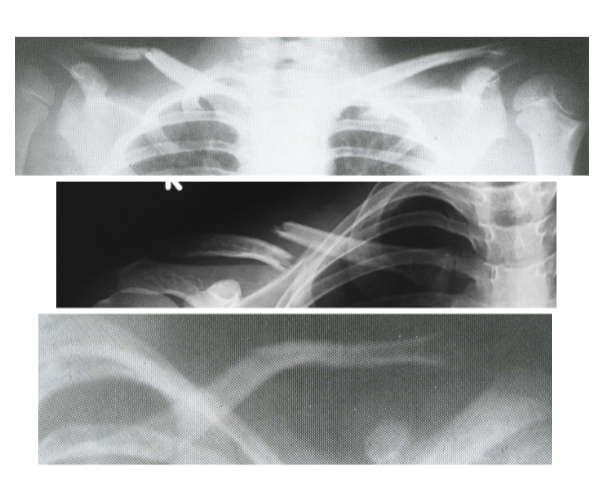

<p>Clavicle Fx </p>

Clavicle Fx

• usually benign

• rare - can also puncture the trachea causing acute dyspnea

Clavicle Shaft Fx

• most common - Greenstick or Complete

• unites quickly - almost always a mal-union

• treatment is with a figure eight harness for comfort not union

• following union - ossification results in a visible anterior lump

Scapula Fx

• associated with high energy/trauma

• other injuries to head, clavicle, spine, ribs

• more commonly seen for chronic dislocation or separation

• very rarely treated orthotically

• immobilization and sling